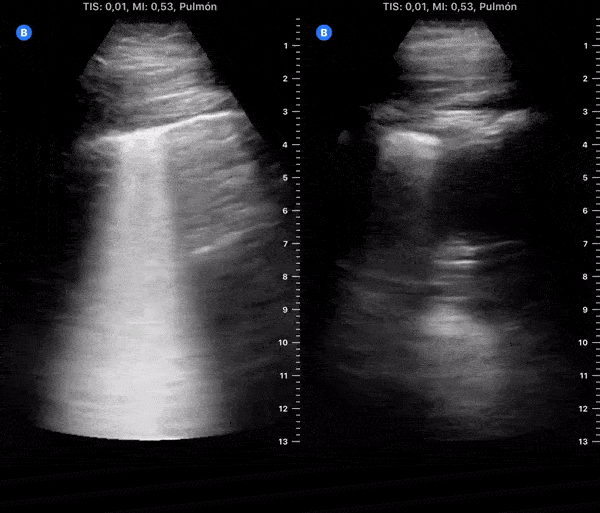

COVID 19 Lung US Disease Progression - Day 8

Day 8 after #COVID diagnosis. Less Cough & similar weakness, still no dyspnea or red flag symptoms. No fever. SpO2 96%. #POCUS update: Right resolved. Left lower lobe much better. Left lateral appeared new focal B-lines. @yaletung